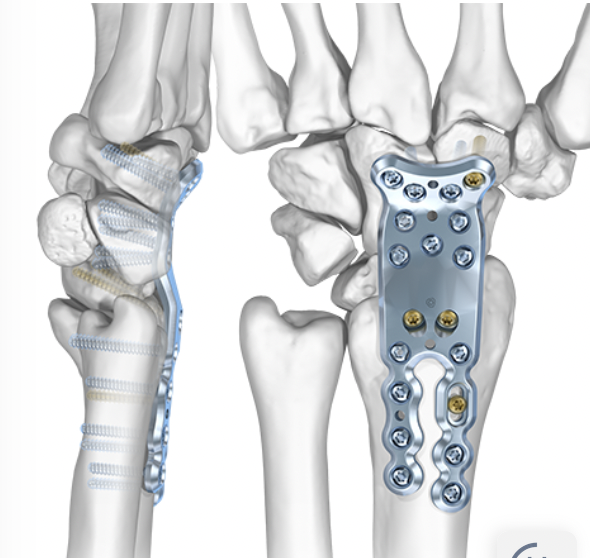

Non spanning dorsal plate

Concept

Sparing 3rd carpo-metacarpal joint

- may reduce tendon rupture / 3rd metacarpal periprosthetic fracture

- ? indicated if CMC osteoarthritis

- ? non spanning increases nonunion rates

Technique

Medartis CMC sparing wrist fusion plate